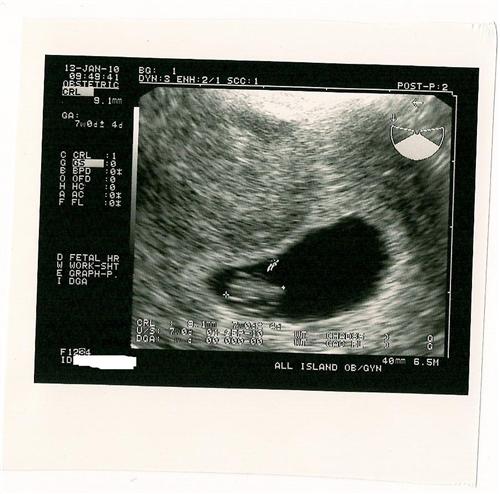

Just got back from my second sonogram

I am 7 weeks today. A little further along than we thought. Due Sept 1

One more sonogram with my RE and he will release me to my OBGYN.